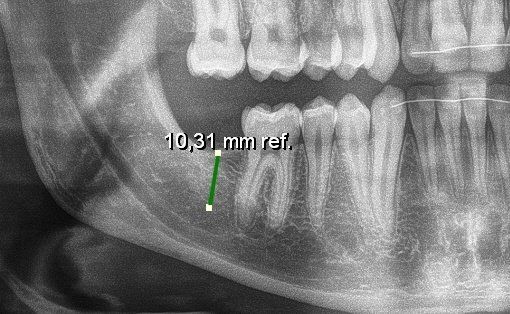

Die digitale Bildauswertung bringt weitere Vorteile: Wir können Bilder vergrößern, verschiedene Filter zur Diagnostik einsetzen, digitale Vermessungen vornehmen und unsere Bilder in exzellenter Qualität digital an Kollegen schicken, die diese Bilder dann in gleicher Weise analysieren können.

Meßaufnahme für eine Implantation - nur mit Röntgen möglich.